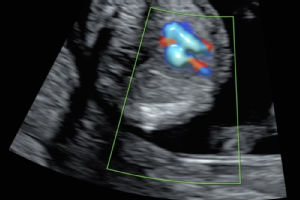

Zur Einschätzung des Risikos für Trisomie 13, 18 oder 21 wird eine Nackentransparenzmessung durchgeführt. Dabei wird die Flüssigkeitsansammlung im Nackenbereich des Babys per Ultraschall gemessen.

- Dopplermessungen in den Gebärmutterarterien